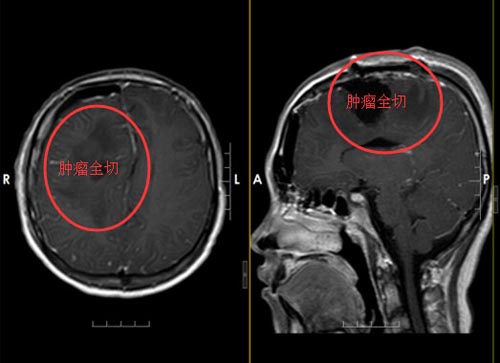

神经外五科医生团队在唤醒麻醉下行“右侧额叶占位性病变切除术”,术中导航定位,肿瘤囊腔穿刺抽吸黄色液体20ml,调整麻醉剂量,术中唤醒小丽后,确定肢体语言功能均无异常,于右额叶脑组织皮层电刺激确定肿瘤后方运动区边界,切除皮层下部分灰白色肿瘤冰冻,结果提示:高级别神经上皮细胞瘤可能,镜下肿瘤组织全切后,妥善止血,麻醉满意,手术顺利。

麻醉清醒后,小丽神志清楚,回答正确,可遵嘱活动。术后病理诊断为:右侧额叶偏高级别神经上皮细胞瘤,考虑为幕上室管膜瘤可能性大。

▲手术后